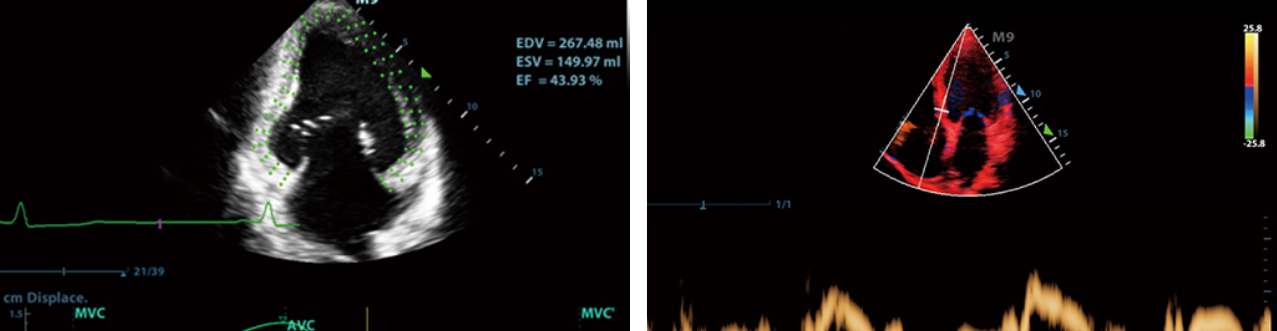

- 4. For the onset of heart disease, support automatic measurement of cardiac function, TDI tissue Doppler assessment of diastolic function, tissue spot tracking assessment of cardiac machine movement, etc.